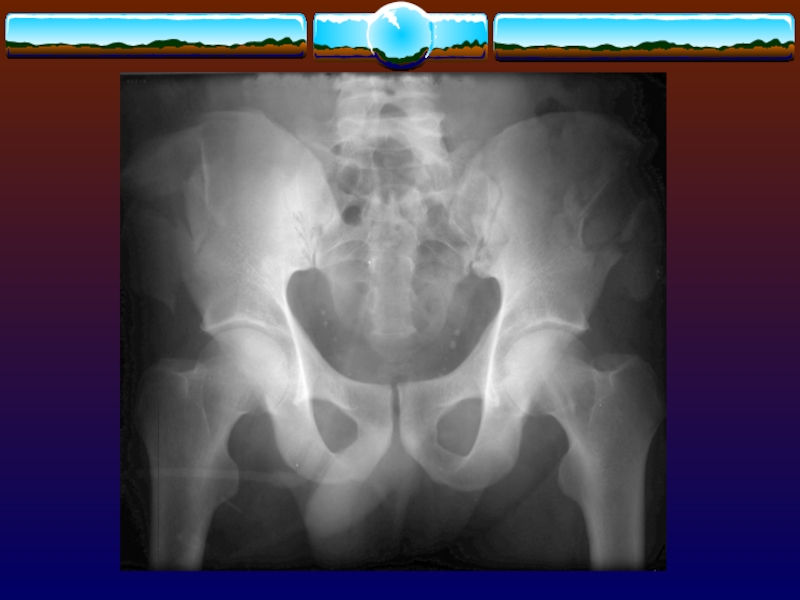

Слайд 68Сопутствующие повреждения при тяжелых переломах.

в 50 % случаев повреждения органов

брюшной полости

в 15 % случаев повреждения мочеиспускательного канала

в 10 %

случаев повреждения мочевого пузыря

Сопутствующие повреждения при тяжелых переломах. в 50 % случаев повреждения органов брюшной полостив 15 % случаев повреждения

Слайд 102 Оценивают вероятность дестабилизации гемодинамики (или исключают эту возможность).

После тяжелого перелома

костей таза в забрюшинном пространстве может скапливаться до 4 л

крови .

Оценивают вероятность дестабилизации гемодинамики (или исключают эту возможность).	После тяжелого перелома костей таза в забрюшинном пространстве может скапливаться